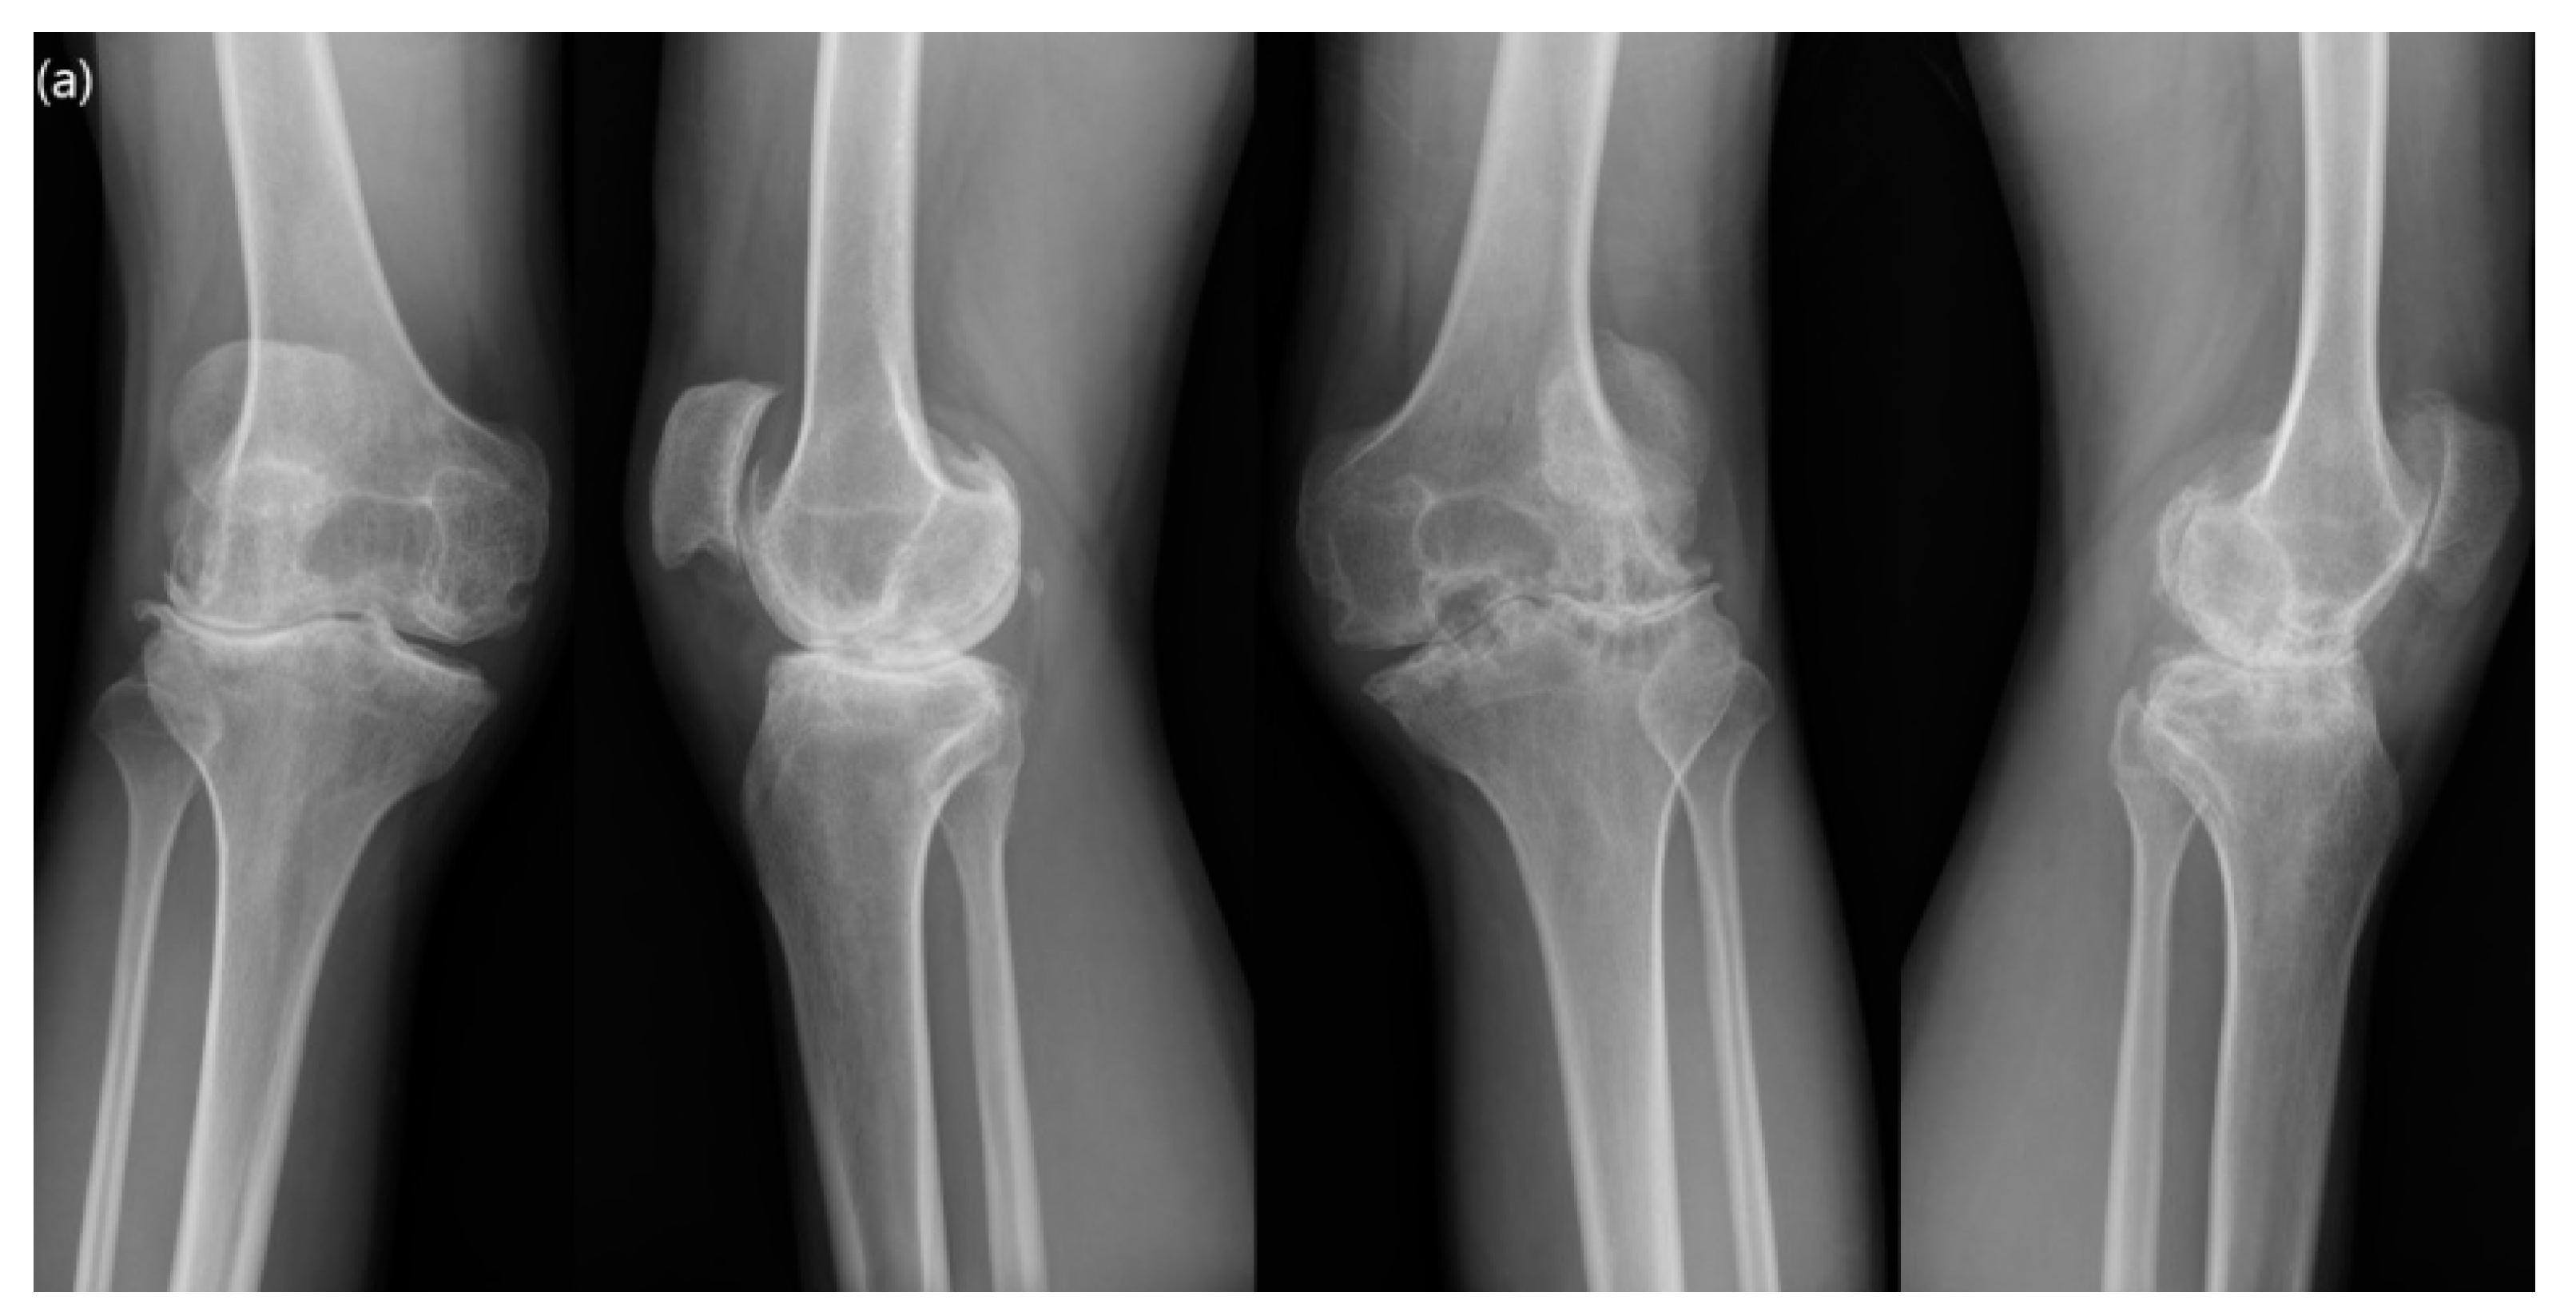

2.2. Operation